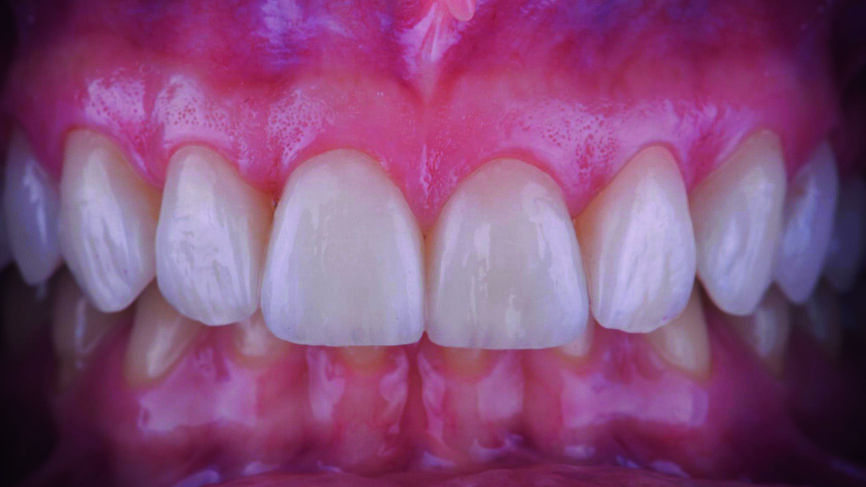

Le jeu de facettes en céramique feldspathique a été fabriqué en IPS Style (Ivoclar Vivadent) sur un modèle en plâtre-pierre, tandis qu‘un bloc IPS Empress CAD Multi (Ivoclar Vivadent) a été utilisé pour le jeu numérique (Figs. 13 et 14). Les deux jeux ont été évalués en bouche avec une pâte d‘essai afin de comparer les propriétés optiques des facettes feldspathiques et des facettes réalisées en technique CFAO (Figs. 15a–c).

Le clinicien et la patiente ont décidé subjectivement un scellement des facettes en céramique feldspathique en raison des légères différences dans la longueur des incisives centrales des deux jeux. Les procédures adhésives ont suivi (Figs. 16a–f) et des photographies intra-orales et extraorales ont finalement été prises une semaine plus tard (Figs. 17a–e).